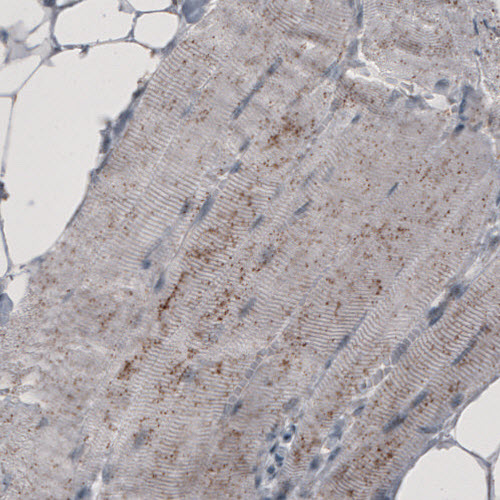

Immunohistochemical staining of human prostate shows granular cytoplasmic immunoreactivity in glandular cells.